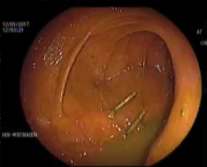

Empiric Colonic Embo Case

Bleeding into diverticulum

Region of bleeding tic

Post embo |